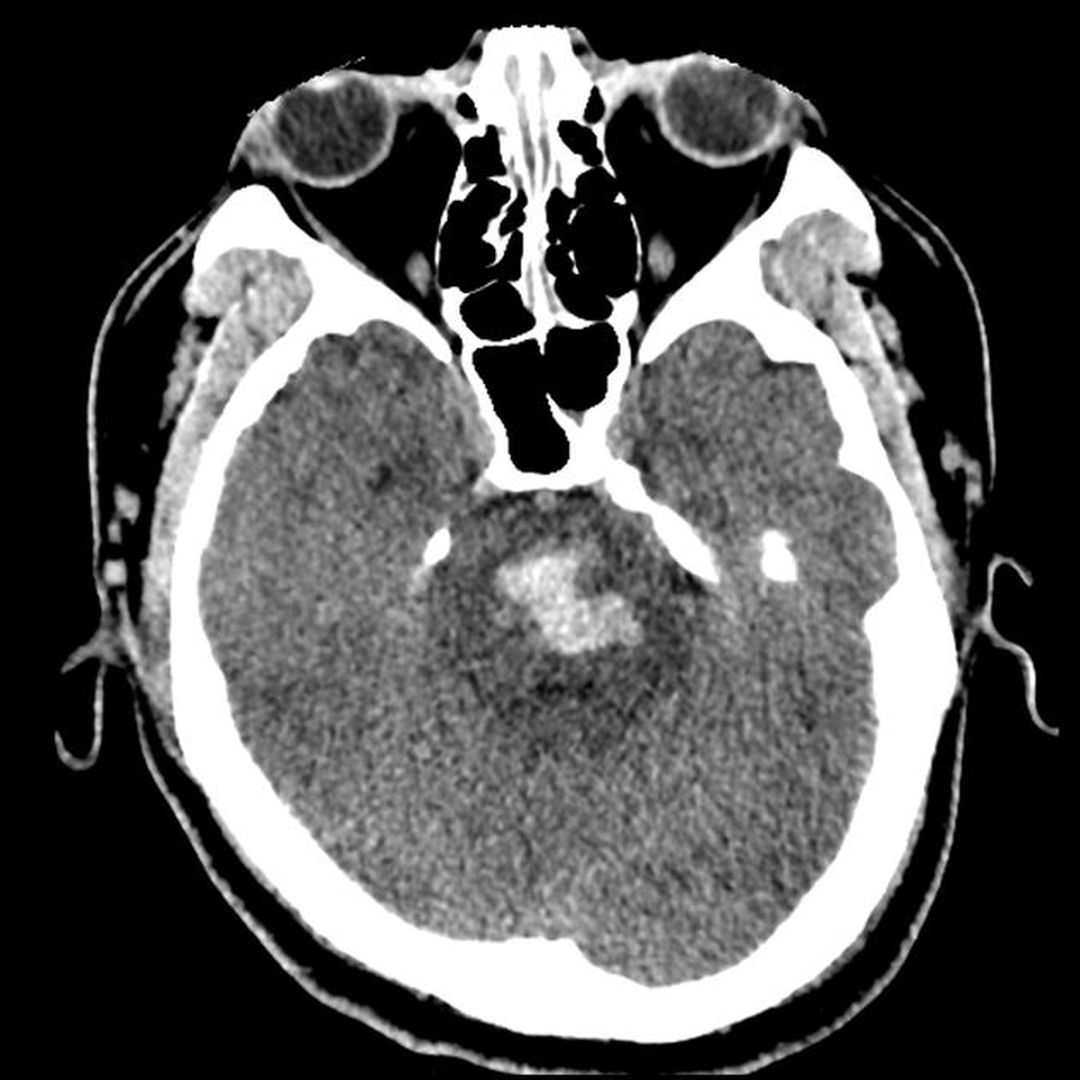

Pontine hemorrhage is a subset of hemorrhagic strokes, accounting for approximately 7% of the cases. The patients present with sudden neurological deficits such as altered mentation, quadraparesis, cranial nerve palsies, seizures, and Cheyne-Stokes respiration. The prognosis is poor if there is excessive bleeding. In case of smaller hemorrhage, the condition is treated medically, and an extra-ventricular drain may be inserted. In case of excessive bleeding, stereotactic clot aspirator may be useful. Source Pontine Hemorrhage https://radiopaedia.org/articles/pontine-haemorrhage#:~:text=Pontine%20hemorrhage%2C%20a%20form%20of,carries%20a%20very%20poor%20prognosis. Image via https://radiopaedia.org/articles/pontine-haemorrhage#:~:text=Pontine%20hemorrhage%2C%20a%20form%20of,carries%20a%20very%20poor%20prognosis.